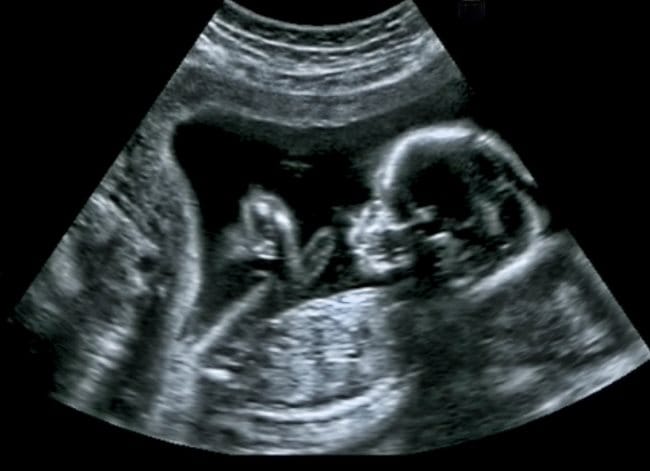

Namun, penyakit ini bisa diketahui sejak dini melalui USG selama masa kehamilan dan pemeriksaan genetik. Pemeriksaan genetik ini bisa dilakukan sebelum pernikahan, misalnya pada premarital check up.